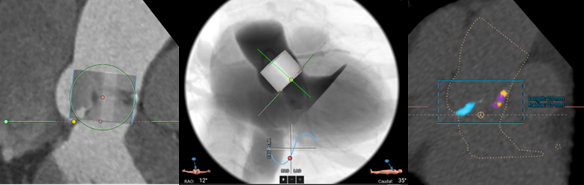

3mensio has established a simplified workflow in which the aortic annulus plane is defined. Coronary heights can be easily measured which is important because coronary obstruction, while rare, can have grave consequences. Also, after choosing the appropriate device size, a virtual valve can be visualized which enables the measurement of the valve to coronary distance (VTC).

“We have been using 3mensio since the early days of the VIVID Registry and it has been instrumental in analysing cases and generating the scientific knowledge around valve-in-valve interventions.